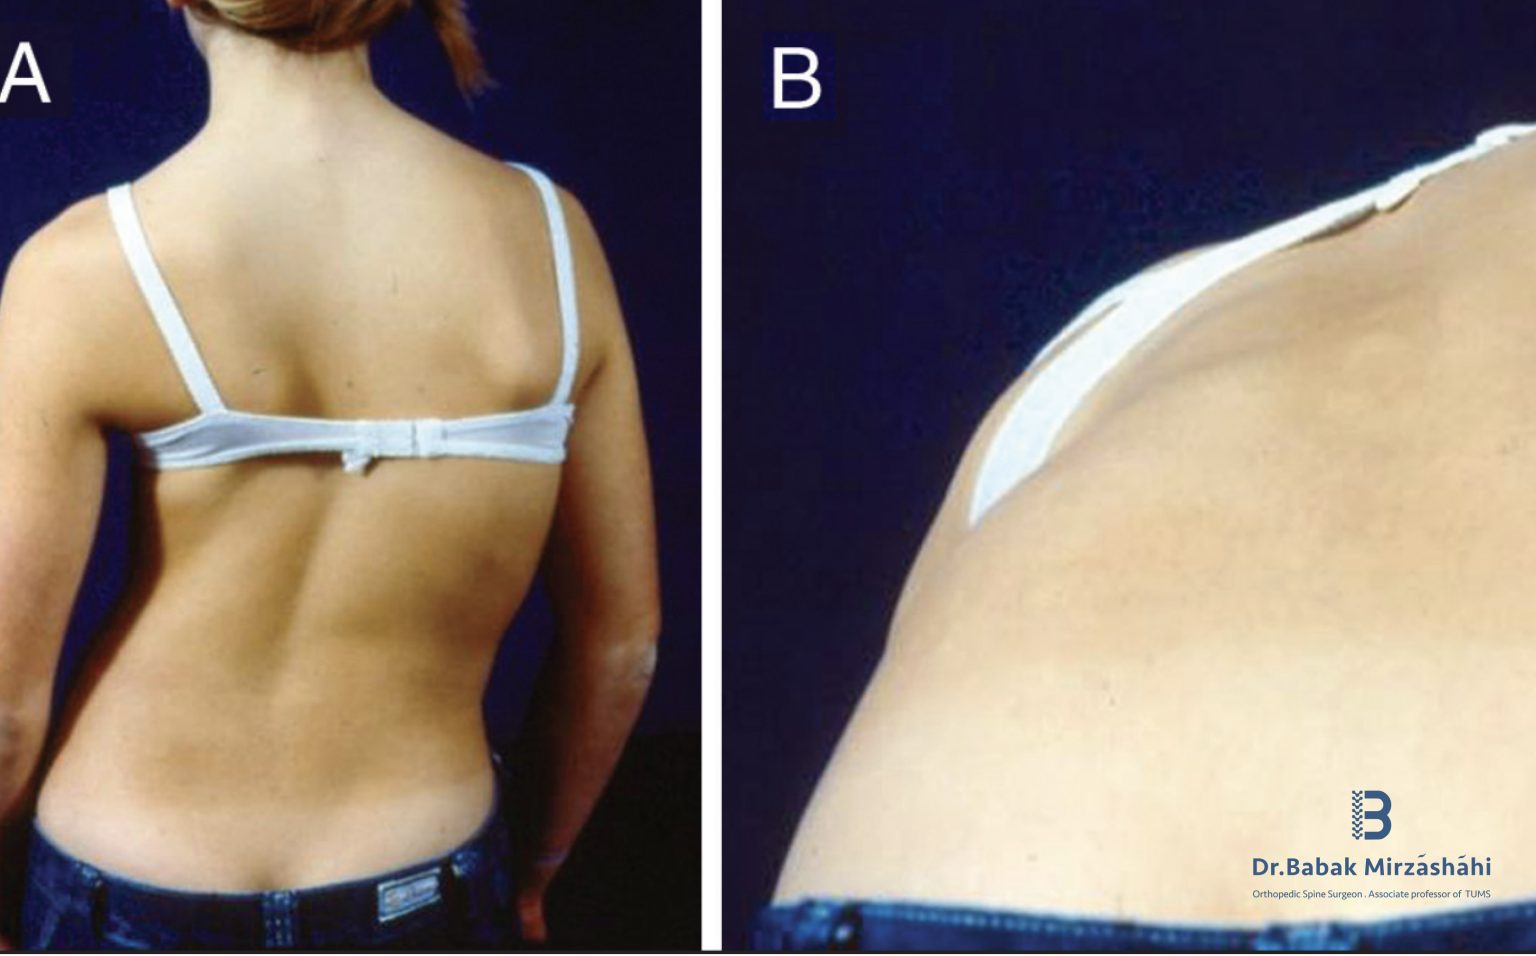

مدیریت درد، کنترل خونریزی و بهینهسازی تغذیه در جراحی اصلاح انحراف و ناهنجاری ستون فقرات مقدمه جراحیهای اصلاح انحراف ستون فقرات مانند اسکولیوز، کیفوز ... ادامه مطلب